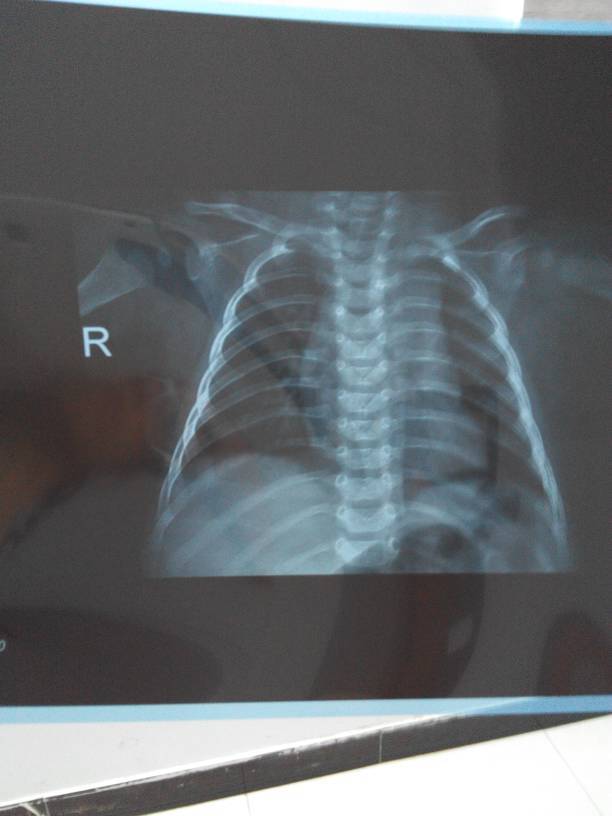

你孩子到底怎么样呀?这个片子我是真的看不清楚。希望你能理解。在医院看片子都是要在观片灯下看的。

你好,胸片只是一个辅助检查,不能单纯依照片子来看病的,还要结合孩子的临床表现及血象检查。再说你传的片子太模糊了,根本看不清。请遵医嘱,积极治疗。